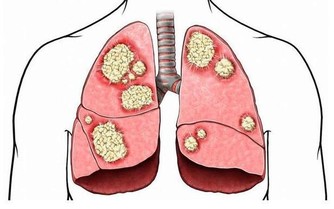

3、保護心臟調查分析表明,堅持午睡,對預防冠狀動脈心髒病和心肌梗塞有積極作用。

一份發表在《內科年鑑》上的報告顯示,每天午睡30分鐘,每週睡三次午覺的人,死於心髒病的機率比不午睡者低37%。

而從中醫的角度來說,午睡也有助於心氣的養護。